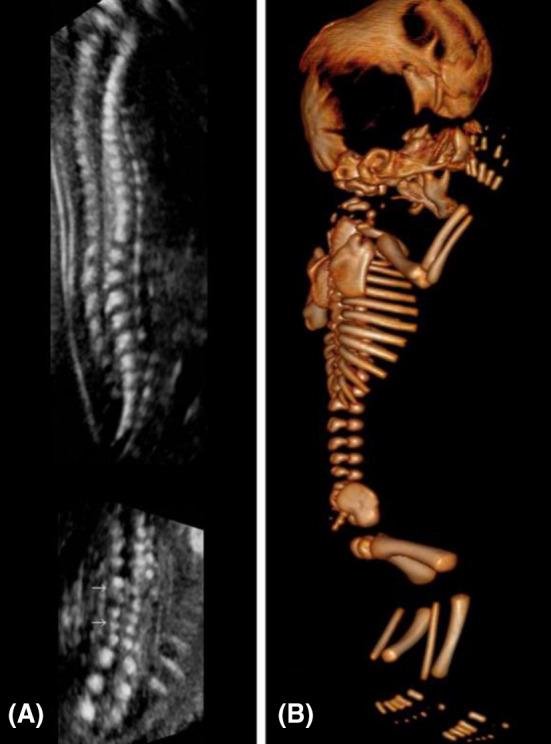

Pfeiffer syndrome (PS) is a rare autosomal dominant genetic disorder characterized by craniosynostosis, broad thumbs / toes. Here, we report a case of PS type 2 with increased nuchal translucency in early trimester.

Pfeiffer综合征(PS)是一种罕见的常染色体显性遗传病,其特征为颅缝早闭、拇指/脚趾宽大。在此,我们报告一例孕早期颈部透明带增厚的2型Pfeiffer综合征病例。